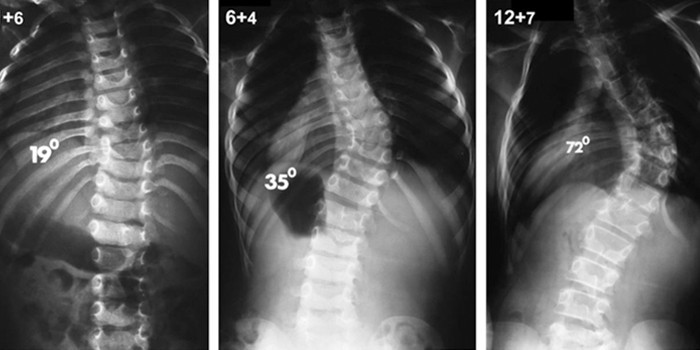

Рентгенография

Исследование помогает установить диагноз, выявить степень тяжести и природу болезни.

При сколиозе делают рентген грудного и крестцово-поясничного отделов в прямой и боковой проекциях.

По назначению врача может быть выполнен снимок в положении сгибания или разгибания позвоночника под определенным углом.

При мягкой кривизне (до 25°) применяют выжидательную тактику. Динамику болезни отслеживают каждые 6–12 месяцев. Если угол изгиба более 45°, рекомендуют ношение медицинского корсета, лечебную гимнастику. При неэффективности этих мер направляют на операцию.